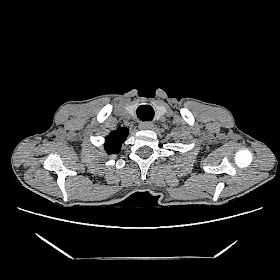

Latest HRCT images: